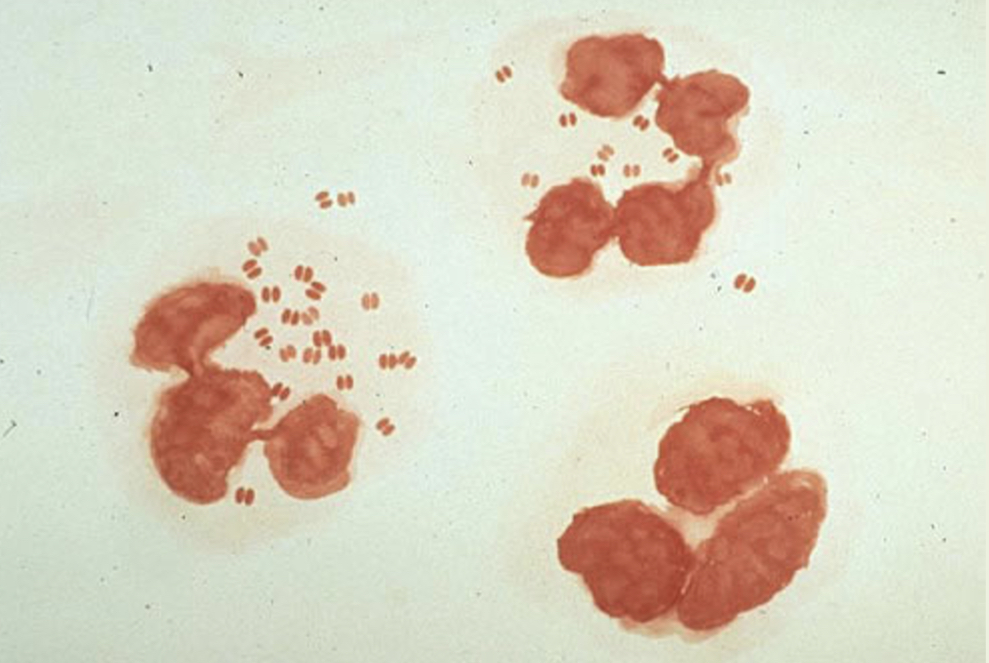

Identify the morphology:

Diplococci